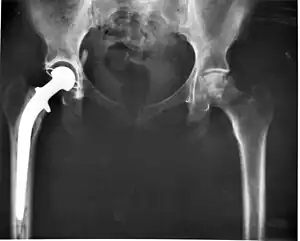

![]() Înlocuirea articulației șoldului | |

În ultimii 45 de ani cel mai utilizat tip de artroplastie este artroplastia endoprotetică, adică înlocuirea articulației cu o proteză articulată numită endoproteză. De exemplu, articulația șoldului poate fi înlocuită total sau parțial cu o endoproteză de șold. Aceasta înseamnă că sunt înlocuite atât acetabulul, cât și capul și colul femural. Acest lucru ameliorează durerea, reface mobilitatea articulară, redă pacientului abilitatea de a merge, crescând astfel și forța musculară.